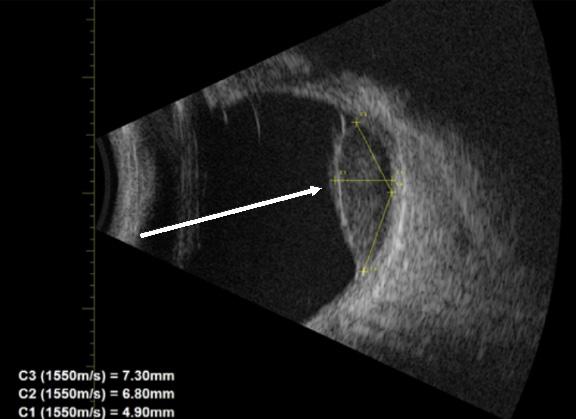

a braided USB-type cord without hub attachments into his urethra. He had similarly inserted foreign bodies into his urethra in the past but stated, “This is the first time I couldn’t get it out.” On arrival the patient was in no acute distress. Genitourinary exam was significant for a single, braided cord protruding from the urethra. Neither the patient nor the emergency physicians were able to extract the cord with gentle traction. Using POCUS, the clinicians identified the cord in the bladder, as well as evidence that the cord had looped within the urethra (Image 3). Urology was consulted, and a urologist evaluated the patient at bedside. The patient

underwent moderate sedation with ketamine. The cord had in fact looped once in the urethra. The cord was extracted by the urologist, with overall no complications besides the looping in the urethra. The patient had residual scant hematuria that resolved at the time of outpatient urology follow-up.